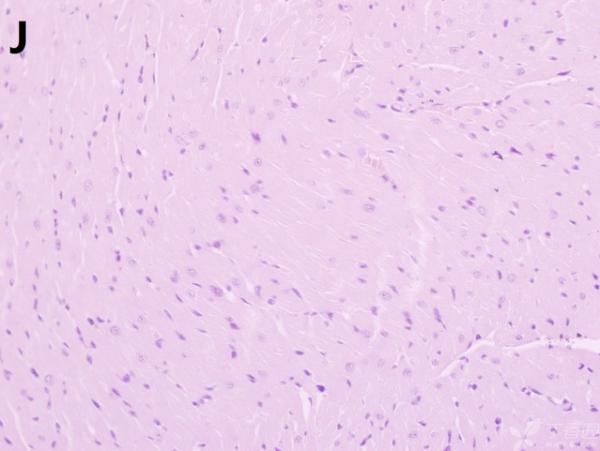

ÎÒ½«Ã¿¸ö×éÖ¯ÅÄÁË3¸öÊÓÒ°£¬ÒÔ±ã×ۺϷÖÎö£¬Âé·³¸÷λ°ïÎÒ°ÑA¡¢B¡¢C¡¢D¡¢E¡¢F¡¢GµÄËðÉË´óСÅŸö˳Ðò ÔÙ°ÑA¡¢B¡¢C¡¢H¡¢I¡¢JËðÉ˵ÄÑÏÖØ³Ì¶ÈÅŸöÐò¡£¸ÃÎÊÌâÒ²ÔÚ¶¡ÏãÔ°ÉÏÇóÖúÁË£¬Á´½Óhttp://www.dxy.cn/bbs/topic/23986562 A1.jpg A2.jpg A3.jpg B1.jpg B2.jpg B3.jpg C1.jpg C2.jpg C3.jpg D1.jpg D2.jpg D3.jpg E.jpg F1.jpg F2.jpg F3.jpg G1.jpg G2.jpg G3.jpg H1.jpg H2.jpg I.jpg I2.jpg I3.jpg J.jpg J2.jpg J3.jpg [ Last edited by ÀëÈËÏæÑÅÀá on 2012-10-9 at 21:11 ] |